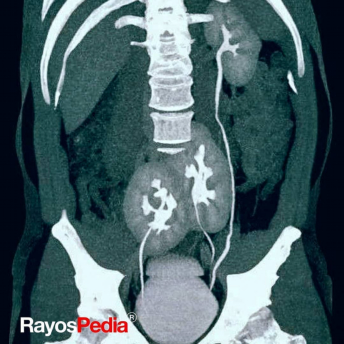

Cuatro imágenes de cálculos renales coraliformes.

Radiografía de una persona con 3 riñones.